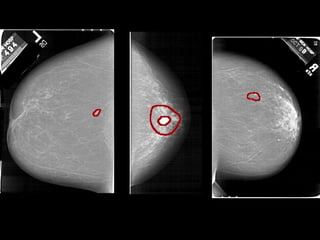

MAMOGRAFIA

RESSONÂNCIA MAGNÉTICA DA MAMA